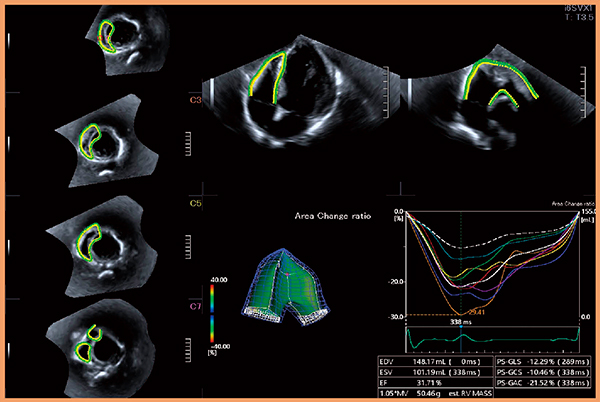

3D WMTでは,2D WMTの欠点である心拍による解析断面のズレの影響が克服され,心臓の動きを三次元的にとらえられるため,より正確に心機能を評価することが可能となる。本機能を右室解析用に発展させた“3D RV Tracking”では,右室を7分画に分割し,局所的な心筋収縮動態評価が可能となる(図8,9)。

図8 3D RV Trackingによる右室機能評価

(画像ご提供:杏林大学・坂田好美先生)

図9 3D RV Trackingによる右室7分割表示